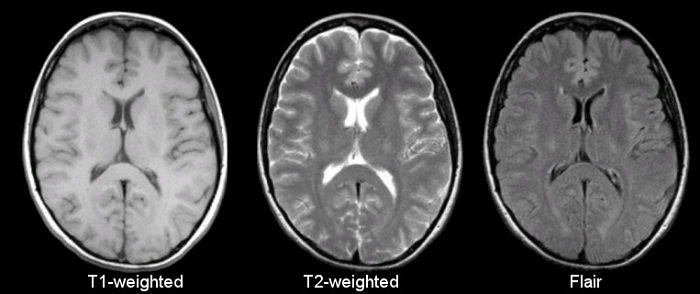

在现实的临床中,CT、MRI、PET/SPECT各种影像都可以用来诊断老年痴呆症。通过比较,脑医生首先选择了MRI图像作为突破口。

王思伦表示:“MRI图像有很多优势:第一,在获取MRI图像时对人体没有放射性损伤。第二,MRI的结构性扫描在临床应用广泛,非常容易获得。第三获取成本低,时间短,通常情况下,患者拍MRI图像的成本在几百元左右,相比于PET\CT要便宜的多,另外拍摄时间短,不会对临床工作带来很多干扰。” 因此美国放射科学会也推荐结构MRI图像是诊断AD(阿尔兹海默症)的最佳影像学方式